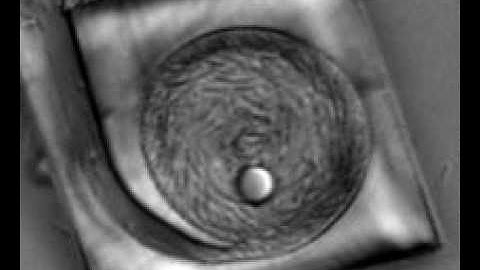

Developing high-throughput microfluidic devices for diagnostic applications